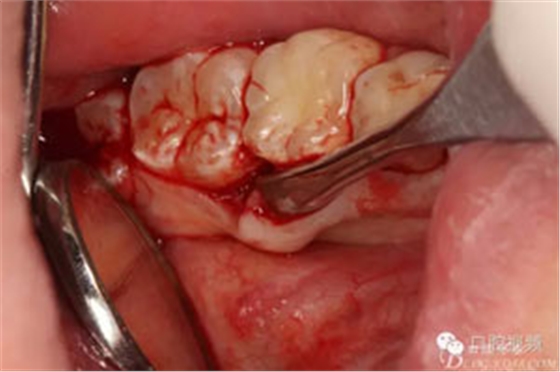

圖6.翻瓣、形成袋形瓣

圖7.通過CBCT準(zhǔn)確定位,暴露35部分牙冠。